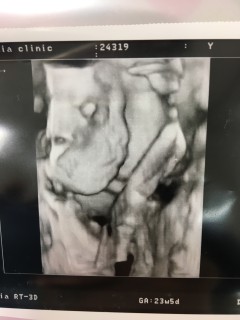

写真:23w5d:みーさん

赤ちゃんが1ヶ月で230gから600gに成長してた!!1ヶ月でこんなに成長するなんて!感激です、これは横顔ですが横顔パパにそっくり!